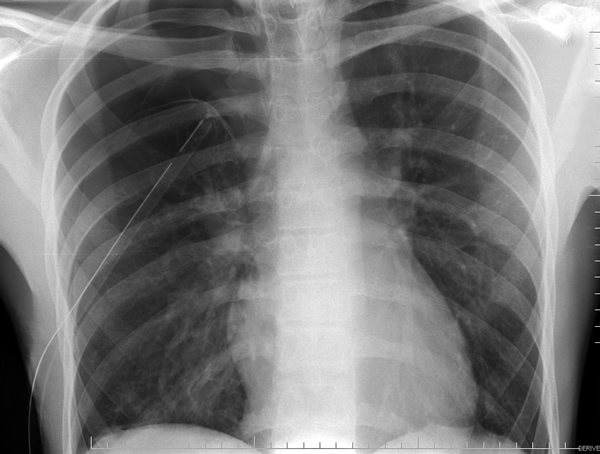

| Figure 4: CT scan showing location of superior segment bleb. |

Patients who have had a previous operation for spontaneous pneumothorax where complete pleurectomy or bleb resection was not performed and who develop a recurrence should be offered re-operation. Prior surgery for pneumothorax is not a contraindication to use of a thoracoscopic approach, as pleural adhesions are relatively few in these patients. A CT scan of the chest readily identifies blebs most commonly seen at the apex of the lung but also in the superior segment of the lower lobe (Figure 4, Video 1 below).